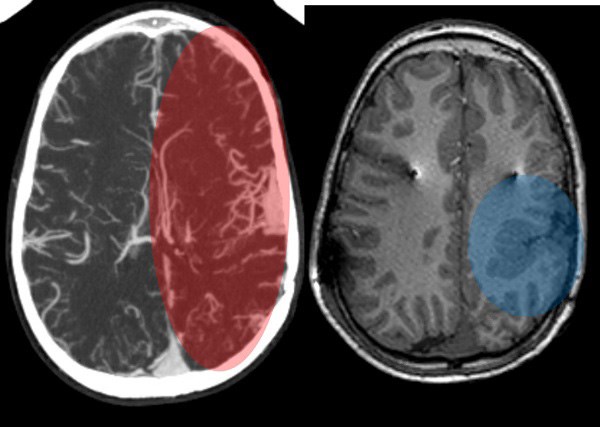

When Lori Dreher was pregnant with Andi, doctors told her that Andi had developed a mass in her brain. While the mass went away during the course of Lori’s pregnancy, Andi was left with complex venous anomaly in the left cerebral hemisphere, which is an unusual or irregular arrangement of veins in the brain. This unique pattern of blood vessels makes attempts at any surgical treatment very high-risk and potentially dangerous. Next to the venous anomaly was also an extensive brain region that spontaneously generated seizures.

Before the surgery, the surgical team took several images of Andi’s brain to create a visualization of the target they needed to reach with the electrodes. The surgery took place on October 1, 2018. Despite being at a high risk for hemorrhage because of her venous anomaly, Andi’s surgery went smoothly and she returned home after a couple days recovery in hospital.